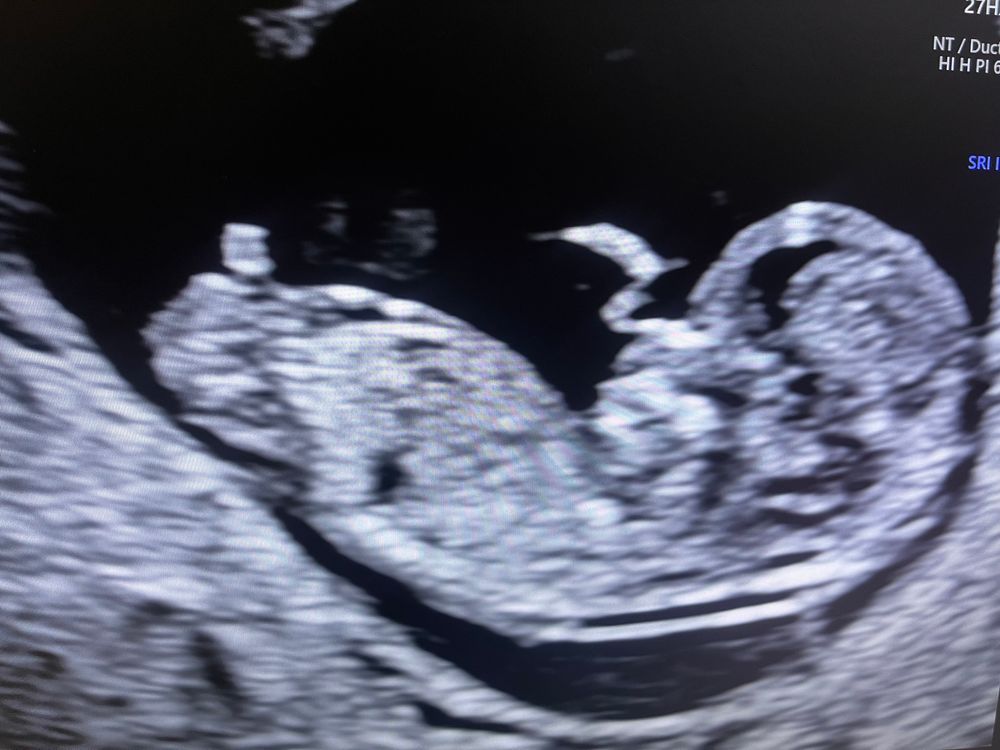

1-ый скрининг

Половой бугорок как у мальчика

Определение пола по фото 11 недель и 5 дней. Пол ребенка в 12 недель